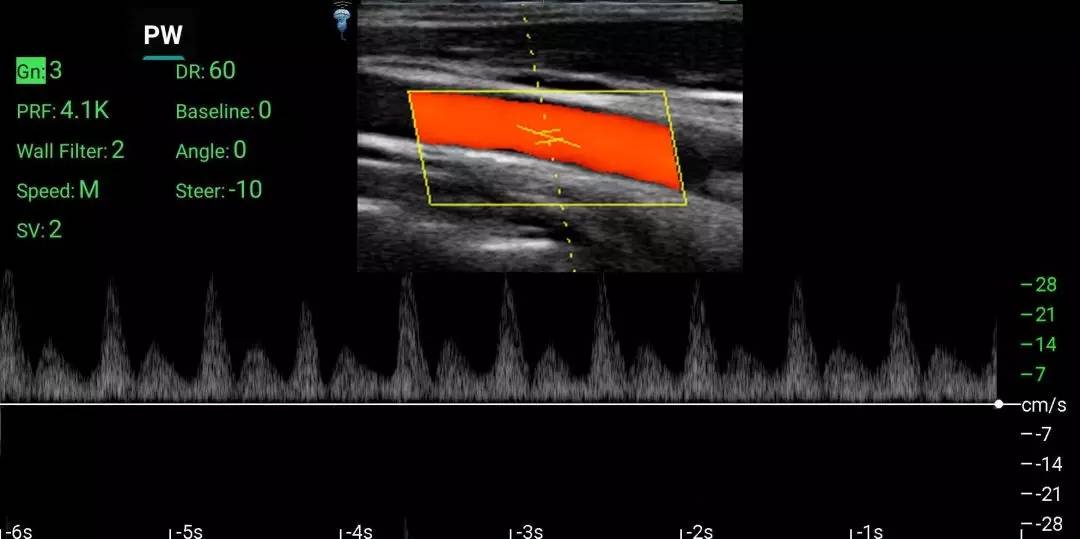

3、PW模式:增益、動態(tài)范圍、PRF(脈沖重復(fù)頻率)、基線調(diào)節(jié)、壁濾波、角度校正、時間標(biāo)尺、發(fā)射偏轉(zhuǎn)、取樣容積。

智能手持式超聲診斷儀臨床效果圖